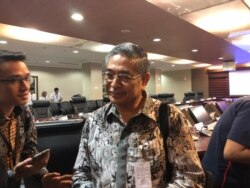

Kepala LBM Eijkman Profesor Amin Soebandrio kepada VOA mengatakan plasma darah hanya dapat diberikan kepada pasien yang terinfeksi virus corona, yang kondisinya parah atau berat. Jadi tidak dapat digunakan untuk pencegahan yang sifatnya individual.

“Jadi misalnya tidak bisa orang yang sehat kemudian karena takut terinfeksi virus corona terus dia minta disuntik plasma itu tidak bisa . Jadi ini betul-betul untuk pasien yang sedang sakit berat karena terinfeksi virus corona. Itu juga harus diseleksi oleh tim dokternya,” kata Profesor Amin.

Lebih lanjut Profesor Amin menjelaskan pada prinsipnya proses pengambilan donor plasma darah hampir sama dengan donor darah. Pada awalnya diambil darahnya sebanyak 10cc untuk diperiksa ada tidaknya infeksi sehingga sampel ini benar-benar aman.

Penyintas Covid-19 yang melakukan donor plasma darah ini, kata Amin, harus memenuhi beberapa persyaratan, baik dari kesehatan umum, periksa hemoglobin (hb) dan sebagainya untuk memastikan tidak ada virus corona maupun bakteri lain.

Apabila semuanya bagus dan memenuhi kriteria maka dilakukan pengambilan plasma atau yang disebut dengan plasmaferesis. Plasmaferesis merupakan pengambilan, pengobatan, dan pengembalian atau penukaran plasma darah atau komponennya dari dan ke dalam peredaran darah.

“Kalau memang bagus dan memenuhi persyaratan kemudian baru dijadwalkan untuk pengambilan yang 200cc bisa sampai 500 cc, tergantung berat badan pendonornya juga kondisi-kondisi lain, artinya PMI menentukan jumlah darah yang diambil. Sel darahnya akan dikembalikan lagi ke pendonor,” ujar Profesor Amin.

Profesor Amin mengatakan semangat para penyintas Covid-19 untuk ikut mendonorkan plasma darah mereka sangat tinggi.